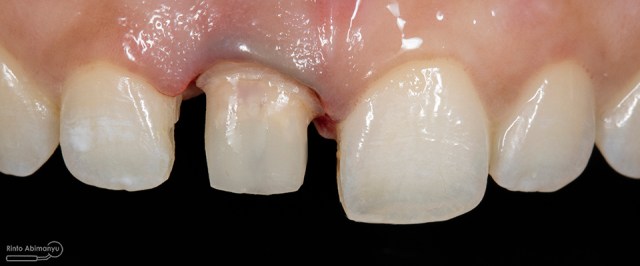

Begini kondisi klinis saat datang…

Foto klinis gigi-gigi anterior yang mengalami fraktur

Dari pemeriksaan radiografis lokasi fraktur menyerempet kamar pulpa pada ketiga gigi tersebut… Saya sampaikan kepada pasien bahwa ketiga gigi tersebut memerlukan perawatan saluran akar terlebih dahulu baru kemudian dilanjutkan dengan restorasi indirek… kenapa saya pilih restorasi indirek? Pertimbangannya adalah sisa struktur mahkota gigi yang ada bila hanya di “sambung” dengan restorasi direk dalam jangka panjang rentan mengalami kerusakan, yang kedua pemilihan warna akan lebih maksimal pada kasus ini…. Pasien setuju dengan rencan perawatan yang saya jelaskan…